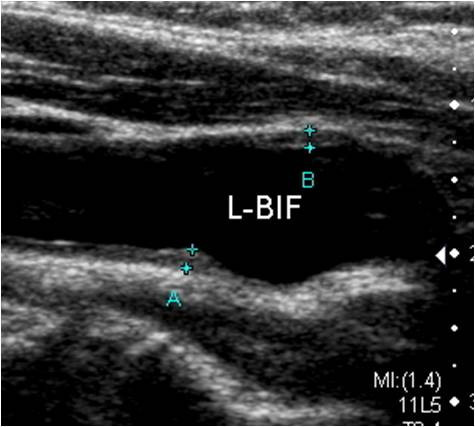

판독 시 중요한 평가 항목은 다음과 같습니다.

- 플라크 위치와 크기

- 협착률(혈관이 얼마나 좁아졌는지 퍼센트로 표시)

- IMT 수치(혈관 노화 및 동맥경화 지수)

- 혈류 속도 증가 여부

- 혈전 또는 혈관 박리 여부